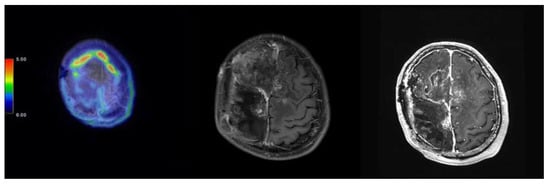

2.1. Case 115

| 115 | 21 August 2020 | 1893 | 14.91 | 11.53 | 8.34 | SD | 28 June 2022, SD | 23 |

| 115 | 74/Male | Meningioma | Skull base | 2.89 | RT + ChemoT |